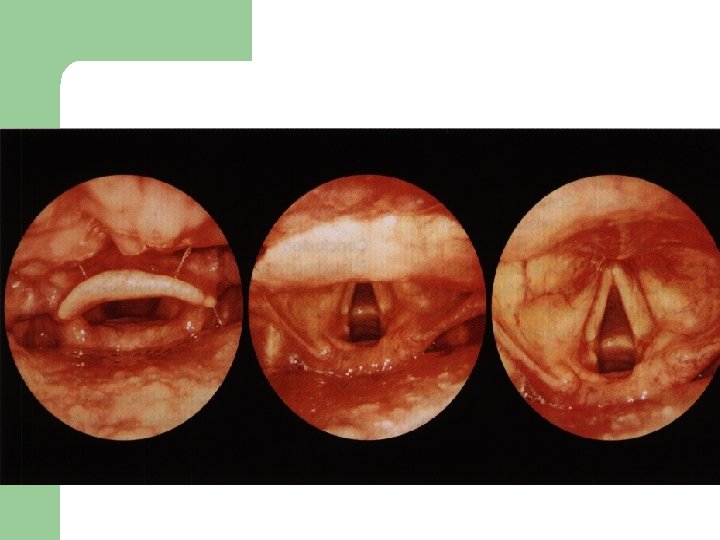

Vývoj dětské chraptivosti l 1. 2. 3. 4. Průvodním jevem při dětské chraptivosti je pokašlávání a pochrchlávání. Nález na hlasivkách postupuje takto: Hyperemické (překrvené hlasivky, Hypertrofické, vřetenovité zduření, hlasivkový uzávěr je neúplný a hlas má dyšnou příměs, ventrikulární řasy se začínají vyklenovat Zpěvácké uzlíčky, nejčastěji na hranicích přední a střední třetiny hlasivek Atrofie hlasivek až s podélnou rýhou, při fonaci nedomykavost uzávěru.

Hlasivkové uzlíky l